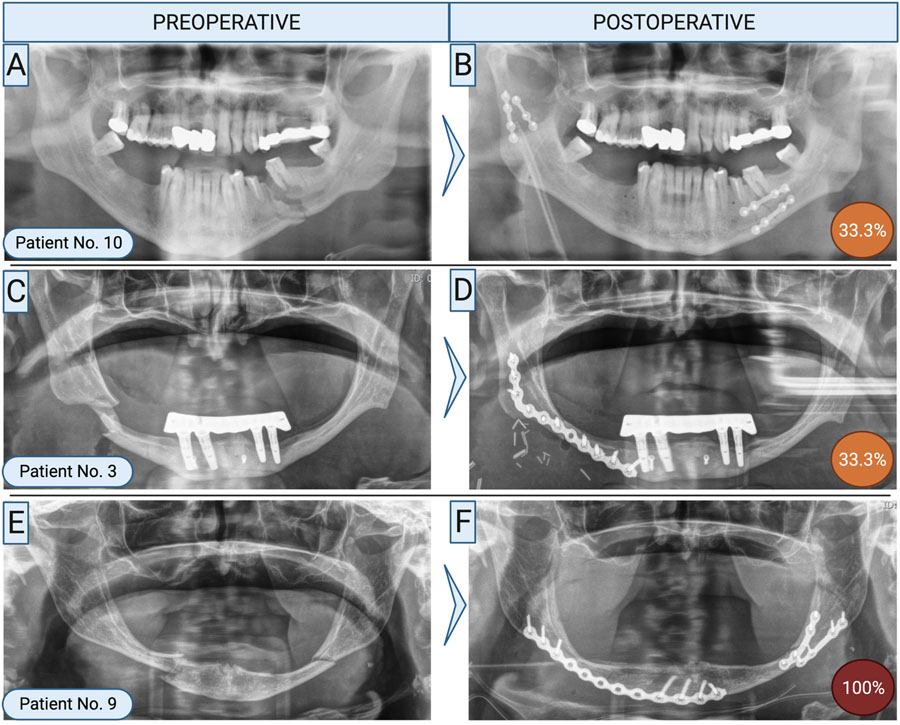

While refixation is a serious complication, it is fortunately rare. General complication rates after mandibular fractures range from 6–22%, but the need for refixation remains low. For instance, Scolozzi et al. reported a 3% refixation rate among 63 patients [2]. In our study, only 17 of 630 patients (2.7%) required secondary surgery. A major concern is delayed presentation—patients often return only after complications like osteomyelitis or abscesses have developed. Despite the low incidence, the consequences of refixation are significant. Revision procedures often require extraoral plating, which increases the risk of nerve injury and typically necessitates extended antibiotic treatment. These secondary surgeries are generally more complex than the initial procedures.

Known risk factors include smoking, alcohol use, drug abuse, and immunosuppression. In our cohort, 64.7% of patients needing refixation had at least one of these factors. However, 35.3% had none—prompting a deeper evaluation. Among these, several patients were found to have received substandard surgical care. To assess this, we reviewed the 17 cases as part of a larger, blinded study using AO surgical principles. In 5 of the 6 patients without recognized risk factors, surgical quality was deemed inadequate—with full agreement among specialists in 3 cases. Our findings underscore not only the relevance of established risk factors but also the critical role of high-quality surgical care in preventing complications.

Yes. All refixation procedures (100%) were associated with fractures in the mandibular body, paramedian, or angle regions. Notably, fractures in the condylar or ramus areas did not result in complications severe enough to require refixation. Furthermore, whether patients sustained isolated or multiple fractures had no apparent influence on the likelihood of requiring secondary surgery.

How was refixation performed?

Refixation was typically prompted by complications such as osteomyelitis or non-union, both of which demanded more invasive surgical approaches. In 82% of cases, an extraoral approach was used, employing load-bearing osteosynthesis techniques. Reconstruction plates were the most common fixation method—47% involved conventional plates, while 41% utilized patient-specific, 3D-printed plates.

Bone grafting from the iliac crest was necessary in about 30% of cases. Intraoral soft tissue conditions likely played a role in the surgical decision-making process, as successful grafting depends heavily on infection-free closure and adequate healing.

On average, refixation was performed 3.5 months after the initial surgery, ranging from 1 to 9 months—consistent with typical bone healing timelines. Patients who could be managed with hardware removal alone were excluded from this study. In some cases, intraoperative evaluation during revision may have revealed sufficient bone healing, negating the need for full refixation. Therefore, refixation was reserved for cases with substantial complications and inadequate osseous healing.